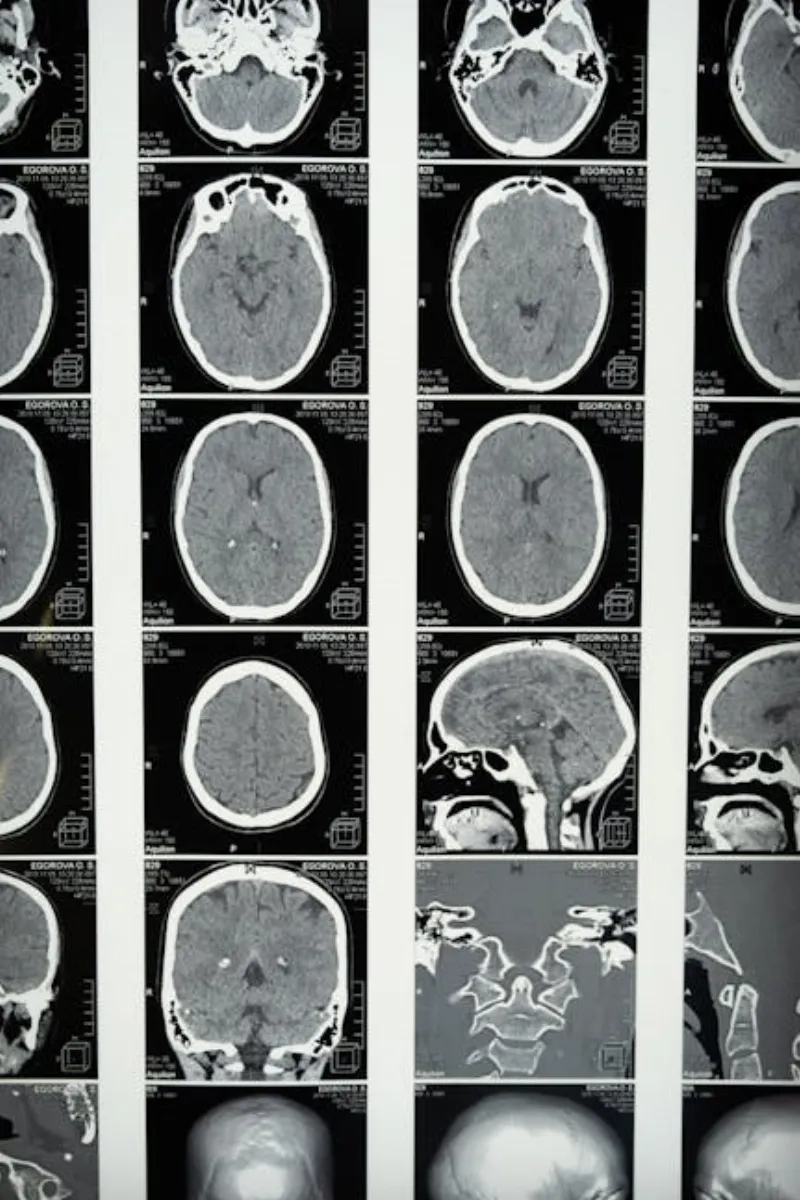

Laut einer Studie, die in der Zeitschrift Nature Communications veröffentlicht wurde, zeigen Gehirnscans, dass die Aktivitätsniveaus in den Anfangsstadien des Schlafs ansteigen. Tatsächlich können bestimmte Bereiche des Gehirns, die an der Verarbeitung von Emotionen und Erinnerungen beteiligt sind, sogar aktiver werden, wenn wir schlafen. Es ist, als ob unser Gehirn Überstunden macht, um die Erfahrungen des Tages zu sortieren und uns auf morgen vorzubereiten.